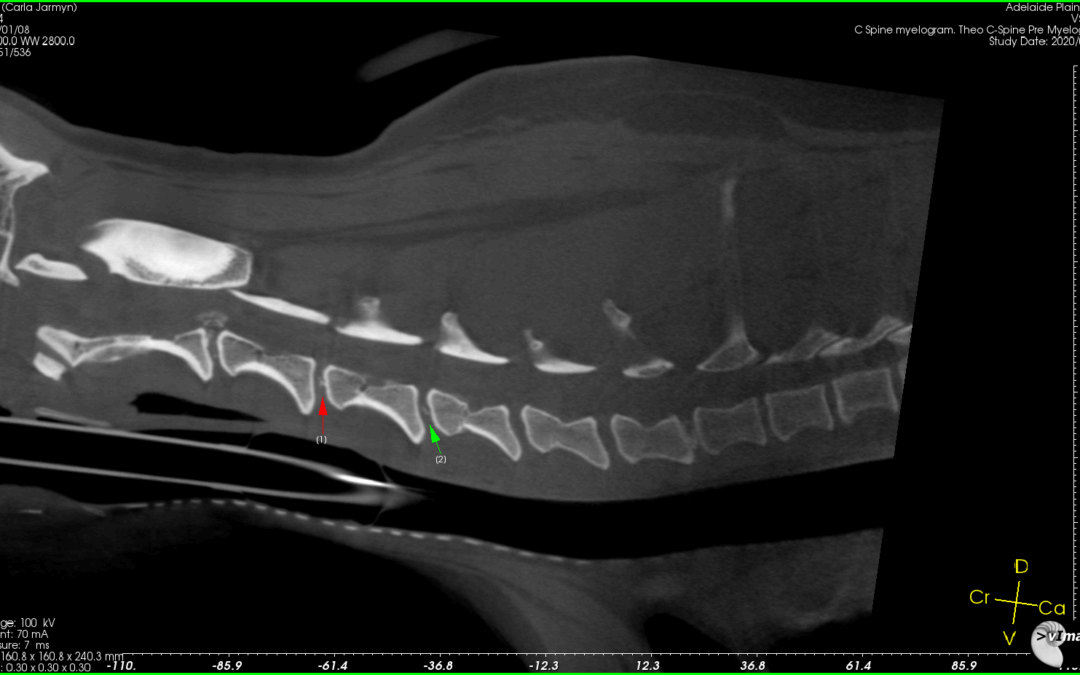

Theo 2

• Theo’s Pain In The Neck